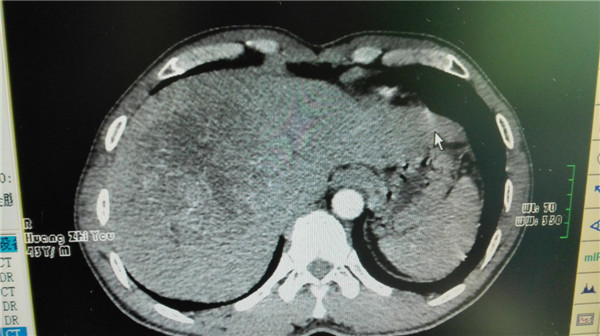

术前肿瘤CT